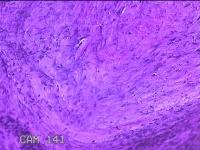

右侧肘后包块

性别

男

年龄

59岁

临床诊断

脂肪瘤

一般病史

发现右侧肘后包块1年余,无明显疼痛及不适。

标本名称

大体所见

灰白暗红色肿物1.3x0.5x0.3cm一个,表面糜烂。